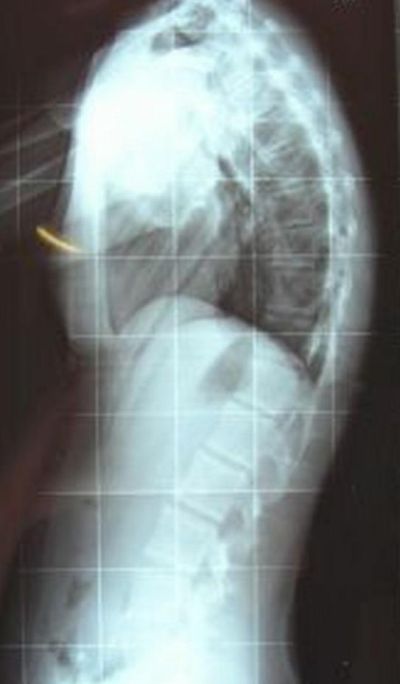

Hier noch ein nettes Bildchen von der WS meiner Tochter

- Morbus Scheuermann 60°

- DSCN0910b.jpg (29.21 KiB) 9039 mal betrachtet

Die WS Deiner Tochter ist tatsächlich höchst behandlungspflichtig! Die Scheuermann-Symptome sind deutlich erkennbar und der Krümmungswinkel ist beachtlich!!!